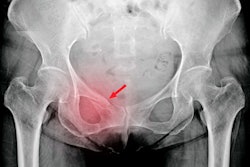

In the retrospective study, a research team analyzed pelvic x-rays of 1,888 emergency room patients to evaluate the model's performance in obtaining fracture results and locations. It achieved an overall accuracy of 92.4%. Compared with general clinical diagnoses, the model substantially improves detection accuracy, according to the authors.

Ping An says the software can detect all fracture types captured on the x-rays, including hip fractures, pelvic fractures, femoral fractures, hip dislocation, and artificial joint peripheral fractures.